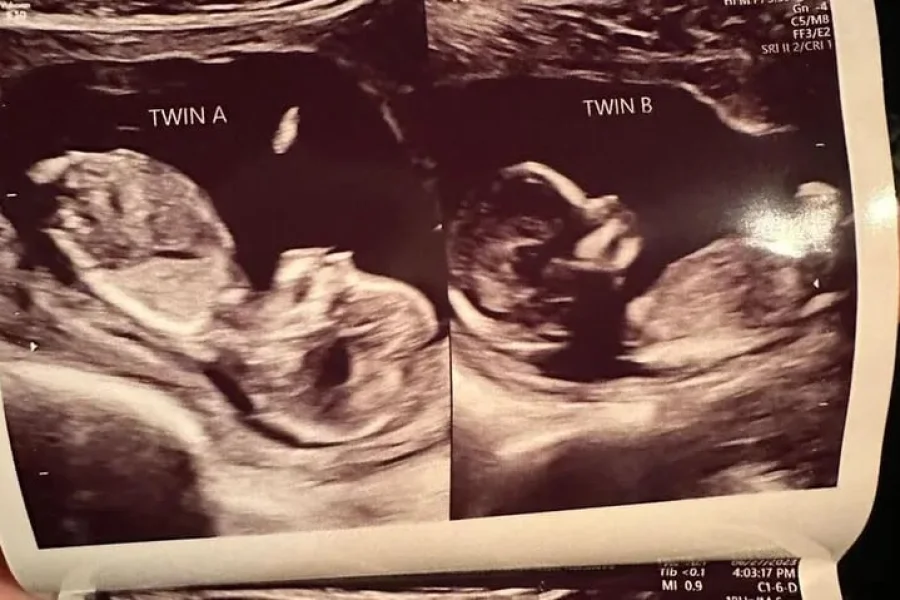

Fue durante una visita ecográfica de rutina de ocho semanas en mayo que la masajista y madre de tres hijos se enteró no solo de que esta vez iba a tener dos hijos, sino que había un feto presente en cada uno de sus úteros.

“¡Nos quedamos un poco impresionados! Durante esa primera ecografía, nos reímos mucho”, escribió en una publicación de Instagram.

Hatcher espera entrar en trabajo de parto y dar a luz natural con medicamentos tanto a la beba A como a la beba B, o “las niñas”, como ella las llama cariñosamente, con una fecha de parto para Navidad. Se dice que ambos embriones están “prosperando”.